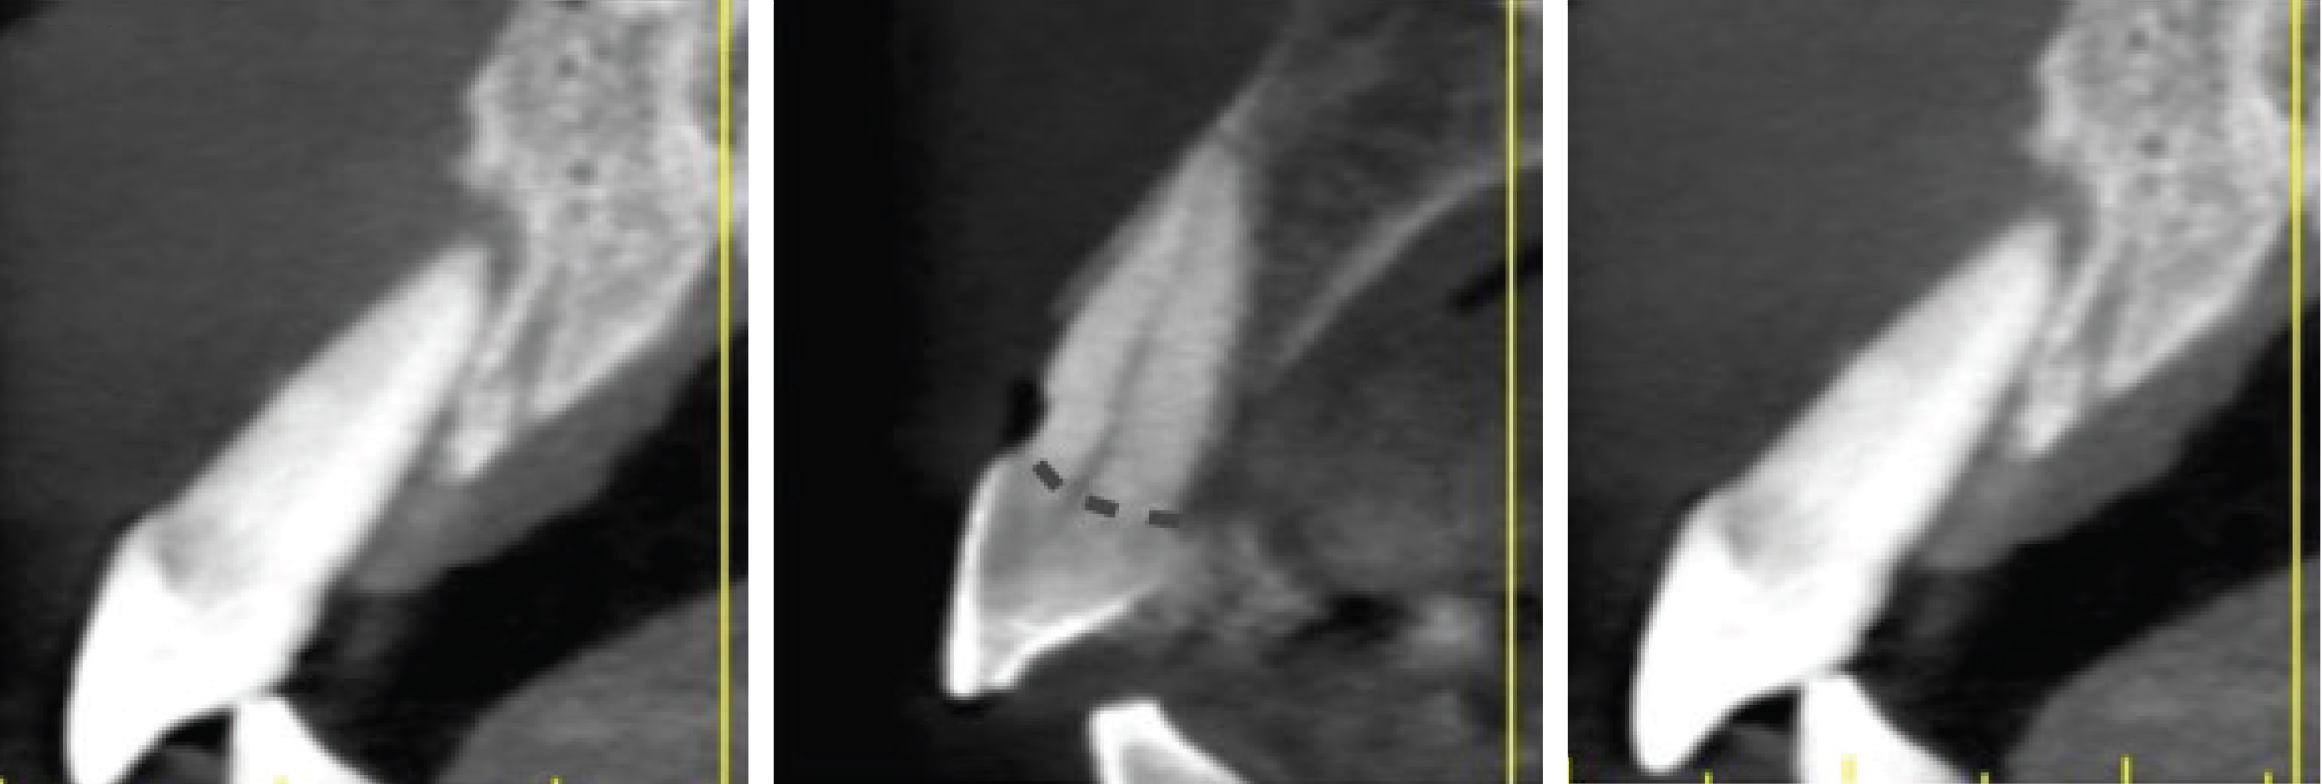

Figure 4

Sagittal cross-sections of CBCT images depicting Grade I (Left), Grade II (Center), and Grade III (Right) sockets. Note the level of the buc- cal plate relative to the cementoenamel junction that is elucidated by this cross-cut.

Grade II sockets are differentiated from Grade I by the amount and quality of the remaining buccal plate. A Grade II socket has a fissure, dehiscence, or deficiency of the buccal plate totaling a 25% to 50% loss. Like Grade I sockets, they have adequate interproximal bone and apical topography (Figure 3, left; Figure 4, center; Figure 5, center).

Grade III sockets are the most deficient and include any socket with inadequate apical topography, insufficient interproximal bone, or more than 50% loss of buccal plate. Inadequate apical topography is defined as not enough bone present apical to the extraction site to allow for implant placement and may be the result of bone loss caused by periapical lesions or concavities due to existing anatomy of the alveolus (Figure 4, right; Figure 5, right). Insufficient interproximal bone is defined as moderate-to-severe periodontal bone loss—greater than 2 mm on one or both of the adjacent teeth.